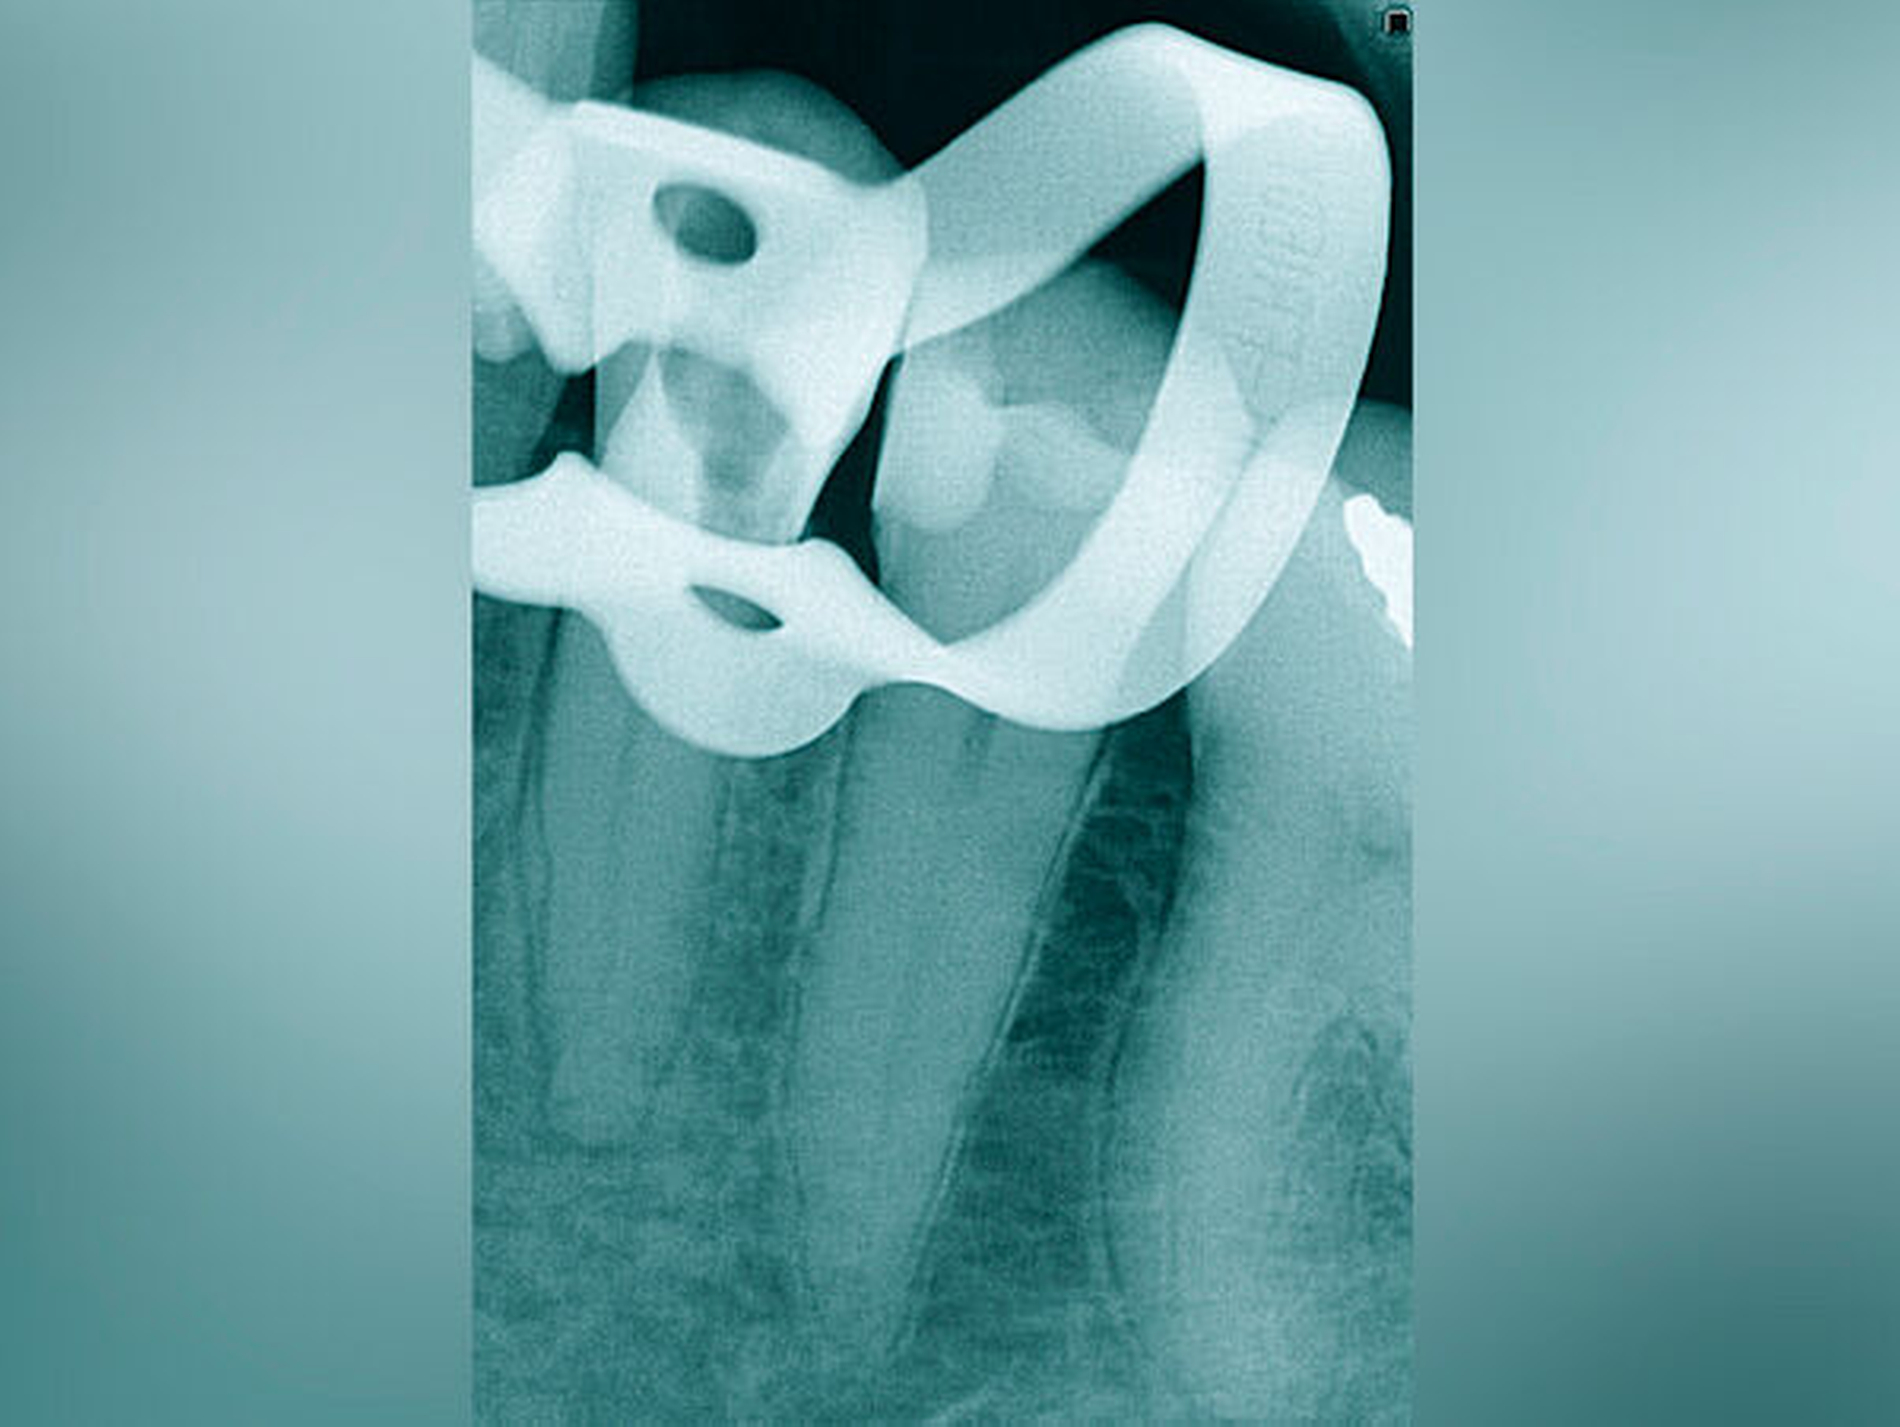

Röntgenbilder können genutzt werden, den anatomischen Schwierigkeitsgrad zu ermitteln. Lässt sich ein Wurzelkanal vollständig bis zum Apex mit einem Krümmungswinkel bis zu 30 Grad und einem großen gleichmäßigen Krümmungsradius erkennen, ist keine erhöhte Schwierigkeit in der Therapie zu erwarten (Abbildungen 1 und 2).

Krümmungsradius: Ist demgegenüber der Verlauf des Wurzelkanals unterbrochen, kann meist mit einer tiefen Wurzelkanalaufteilung gerechnet werden (Abbildung 3) [Reuver, 2002].